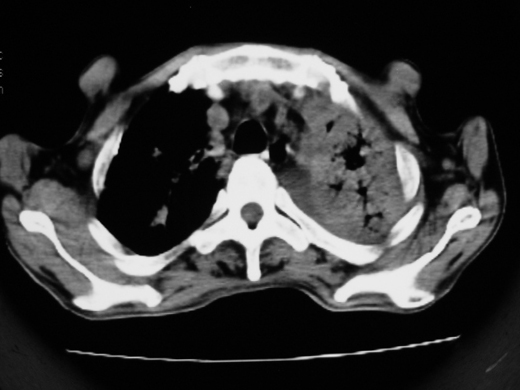

男69岁,年前胸片示肺感染治疗近一月今复查无明显好转,血象正常

右肺多发片絮状结节状及时条索状影,左上肺实变,内可见虫蚀样空洞及支气管气象,左下肺片状及球形病灶,及胸腔积液征象,双肺病灶内多发钙化影,上纵隔向左侧移位,结合病史,考虑双肺继发型肺结核,左胸腔积液。

右肺可见大片状、云絮状改变。右肺可见散在类圆形影,以外带多见。左肺实变,其内可见明显支气管走行影。纵隔淋巴结有增大,左侧胸腔积液。考虑1、肺结核;2、肺癌肺转移不除外;3、左侧胸腔积液。